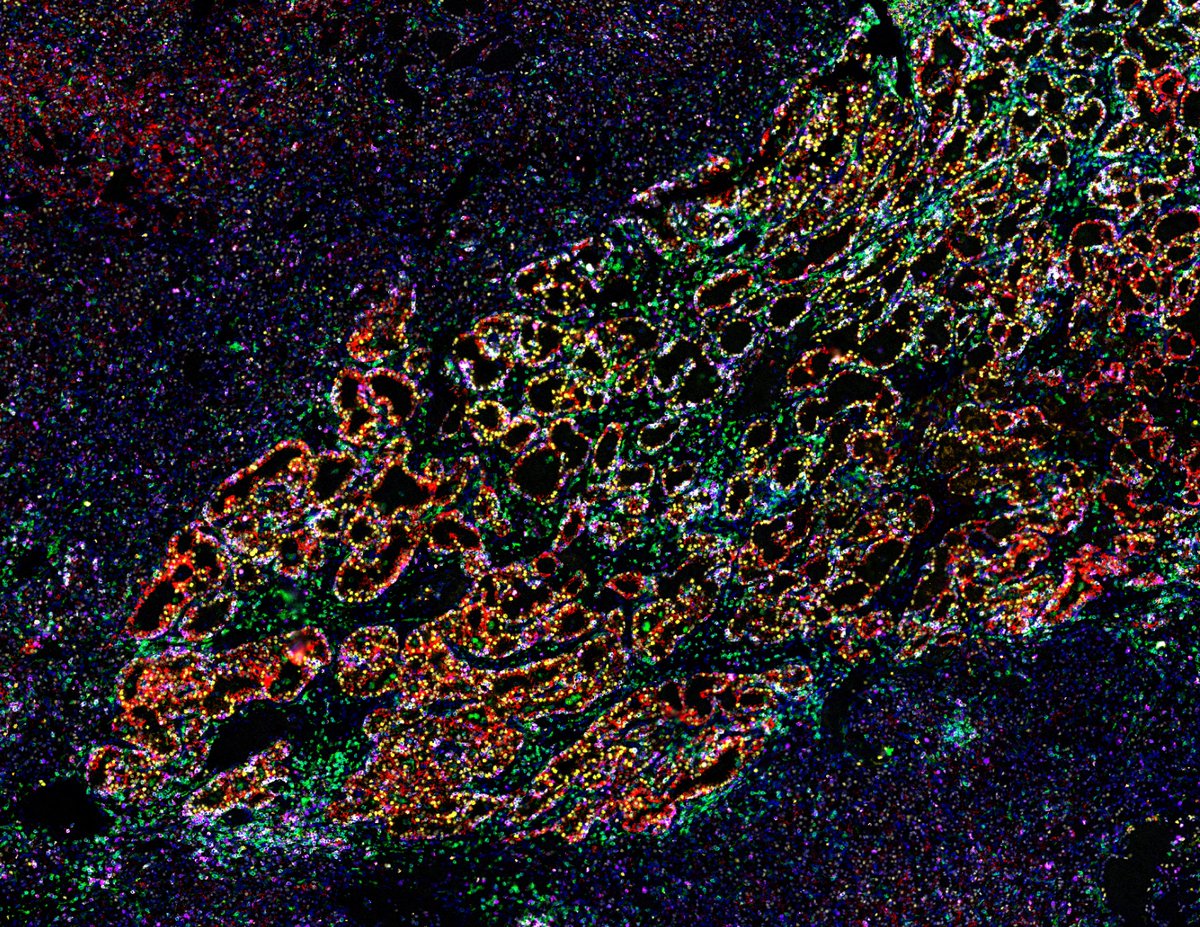

Successful Orion training at @UBC. 🚀 The Poh Lab is using the Orion spatial proteomics platform to map the tumor immune microenvironment in oral cancer.